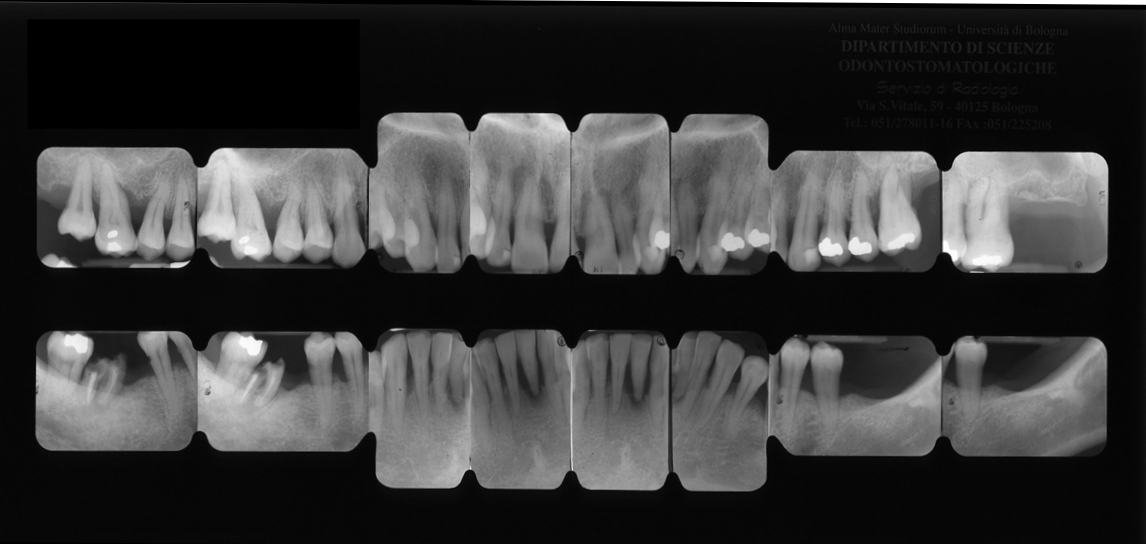

Visita parodontale e radiografie endorali

Va precisato che la visita parodontale acquisisce forza e valore se accompagnata e preceduta da un set di 16 radiografie endorali che sono di fondamentale importanza, specie per diagnosticare i segni di sofferenza parodontale nonché la presenza di lesioni cariose.

Anche su questo punto va spesa una parola sulla necessità che l’indagine sia accurata, sulla sua esecuzione dove dente e processo alveolare siano ben visibili, sulla tecnica che deve essere “parallela” con lastra diritta e non piegata e nello sviluppo.

In un’epoca tecnologica, controcorrente, preferiamo utilizzare una tecnologia classica che prevede di poter fornire al paziente lastre non digitali e quindi non in dischetto ma radiografie (pellicole radiografiche) che il paziente può portarsi a casa, vederle e farle vedere su qualsiasi visore ed illimitatamente nel tempo ed indipendentemente dal sistema computerizzato usato.